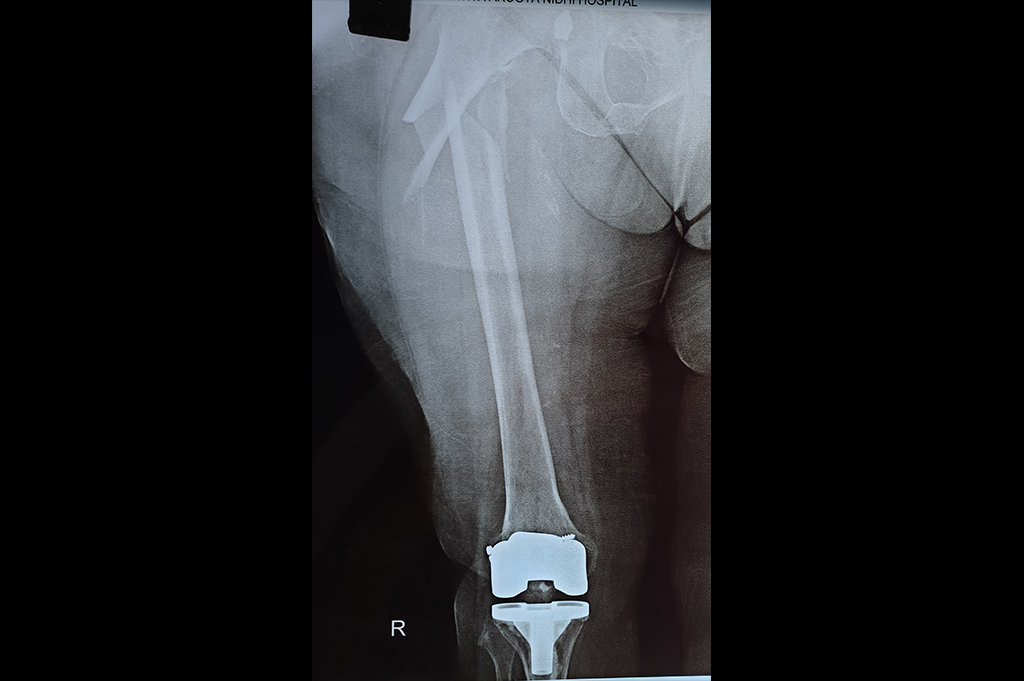

Periprosthetic Fracture THR

Total Knee Replacement - TKR